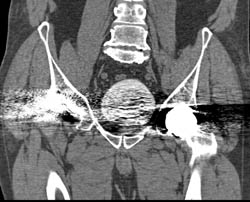

Renal Osteodystrophy